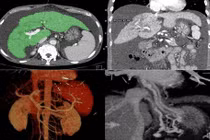

(khoahocdoisong.vn) - Lần đầu tiên tại Việt Nam, Bệnh viện Đa khoa Phú Thọ đã ứng dụng can thiệp TIPS điều trị xơ gan cổ trướng cho bệnh nhân tràn dịch ổ bụng mức độ nhiều, đã từng bị chảy máu tiêu hóa 3 lần.